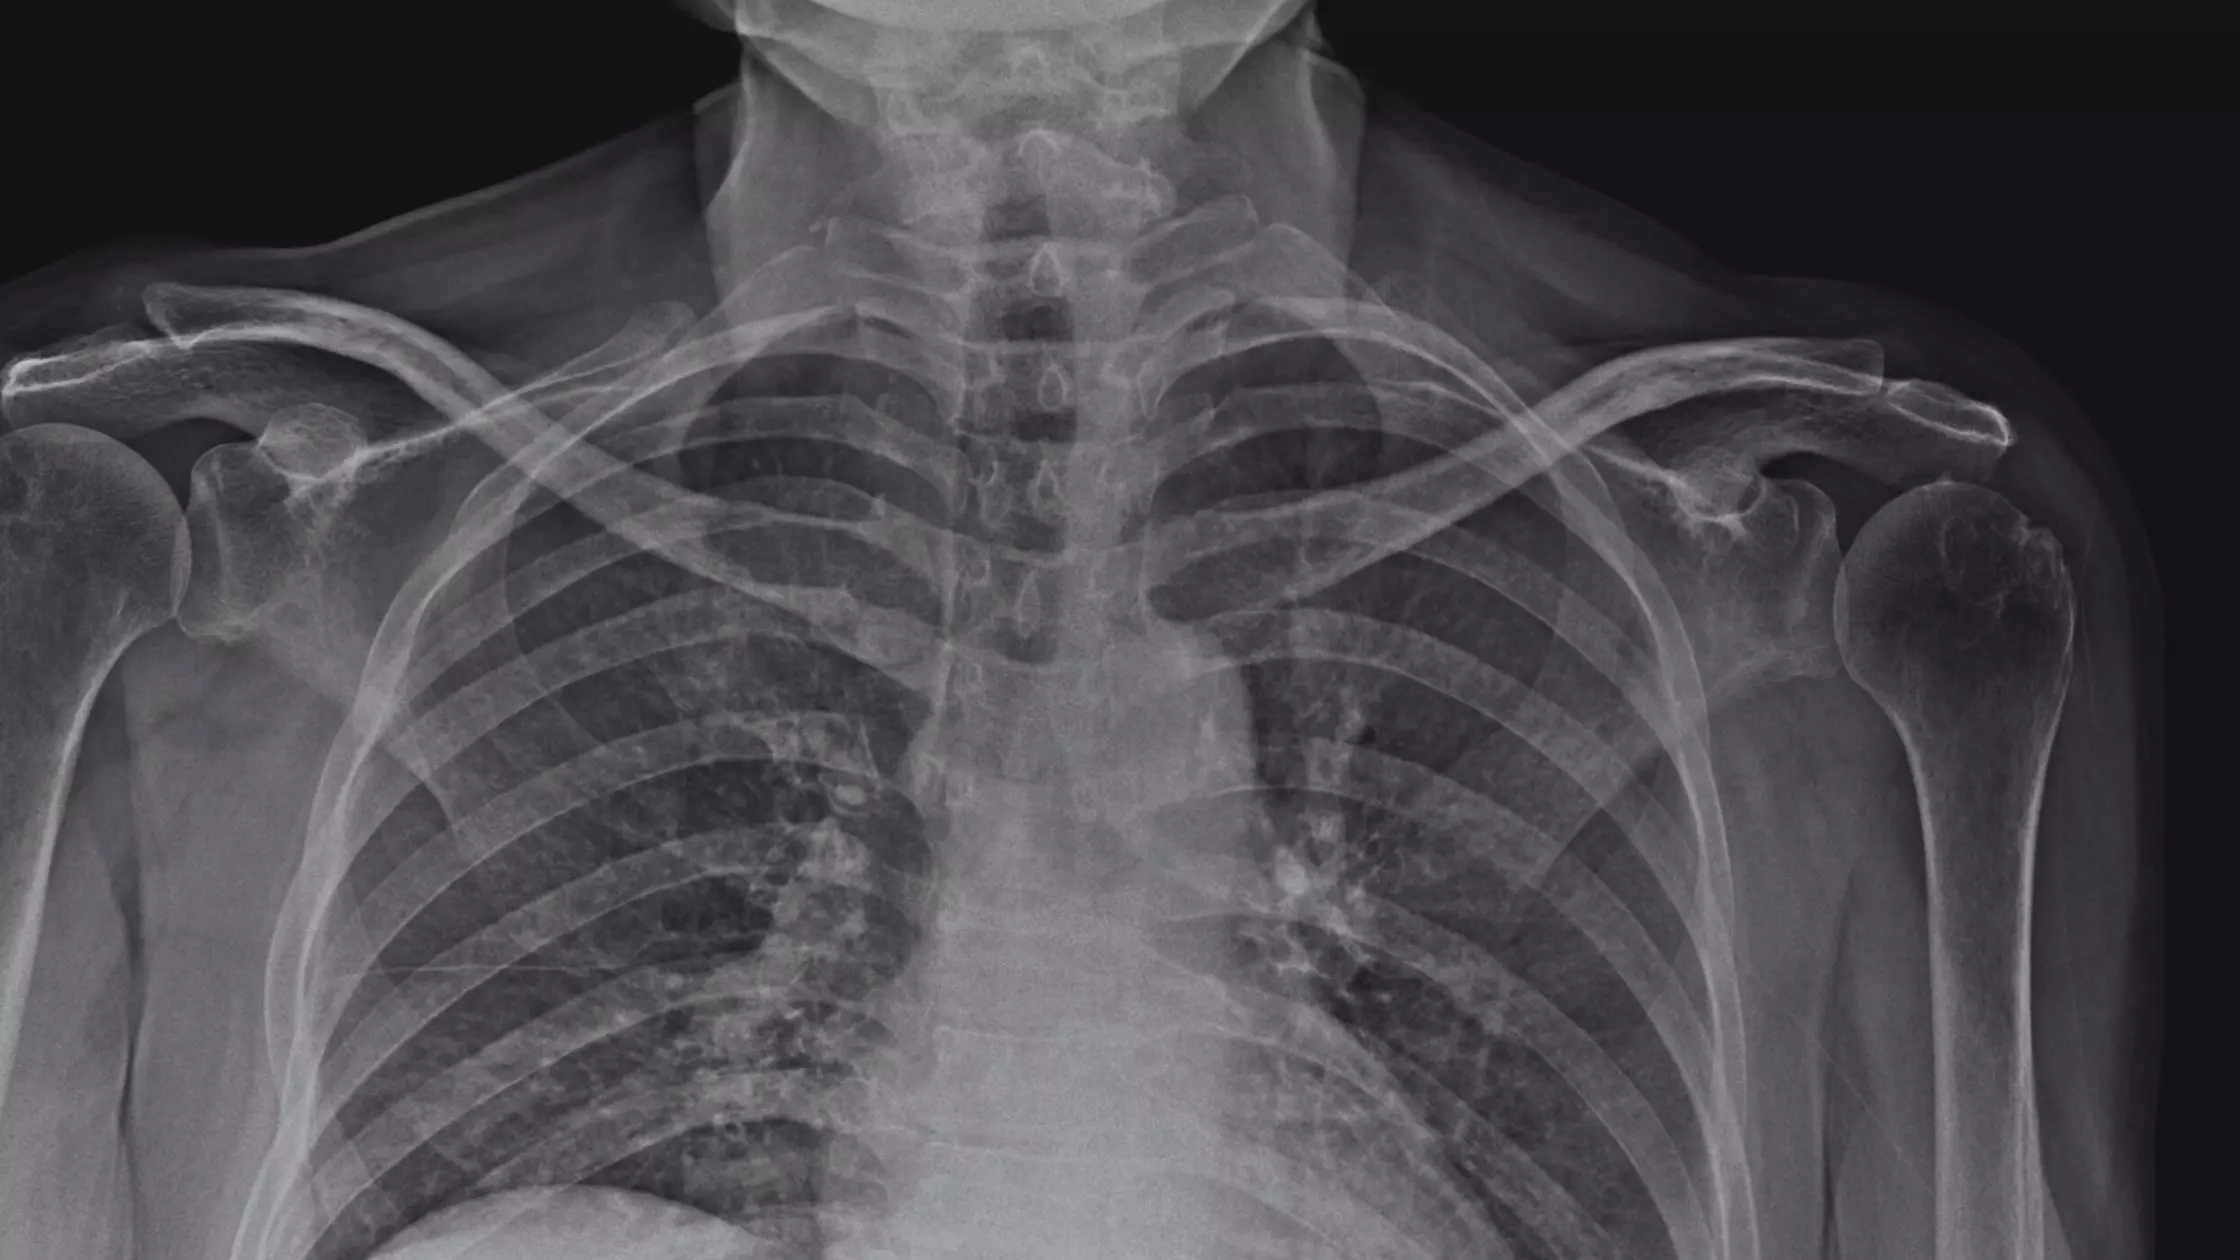

Você pode suspeitar de uma fratura se sentir Dor no Braço, inchaço ou incapacidade de mover o cotovelo ou ombro. O Diagnóstico de Fratura geralmente é confirmado com raios-X ou, em alguns casos, com uma tomografia computadorizada.

As opções de Tratamento do Úmero variam de imobilização com talas ou gesso até a Cirurgia do Braço, dependendo da localização e da gravidade da fratura. A cirurgia pode envolver a colocação de placas, parafusos ou hastes intramedulares.